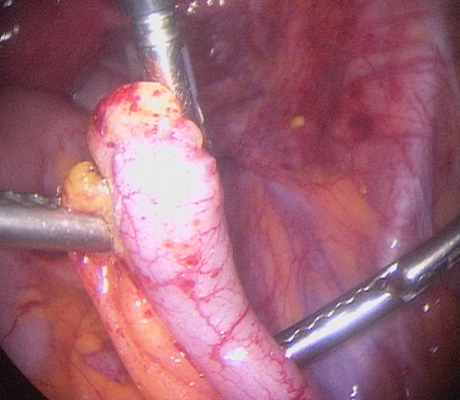

Laparoscopy is an operation (keyhole surgery) conducted under general anaesthesia. A telescope is introduced into a small incision in your navel, other small incisions are made for using special laparoscopic instruments and all the pelvic organs are examined with magnification (Video-laparoscopy) ; then the endometriosis is treated. Video Laparoscopy allows conservative surgery (hysterectomy is NOT the usual treatment for endometriosis) which means laparoscopic excision of the endometriotic implants, with restoration of the normal anatomy and preservation of the uterus, tubes and ovaries.

There are a number of ways as endometriosis may cause infertility. Although women with mild endometriosis may get pregnant, endometriosis is usually a progressive disease, as it gets worse with time. So early diagnosis and treatment is important. Women with advanced disease have low chance of achieving a spontaneous pregnancy. There is plenty of evidence based medicine showing that laparoscopic treatment of endometriosis does improve fertility. When a patient has an ovarian endometriotic cyst associated with infertility, laparoscopic surgery is the first line of treatment. The average pregnancy rate reported after surgery in these cases is 35-50%. So laparoscopic surgery provides a woman with good chances of becoming pregnant spontaneously.